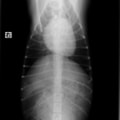

D:胸部レントゲン写真 正面像

左側胸壁心尖部領域を最強点とするLevine 5/6の収縮期性心雑音が聴取された。

胸部レントゲン検査において重度の心拡大と肺水腫が認められた。超音波検査では、重度の僧帽弁閉鎖不全症、三尖弁閉鎖不全症、中程度の大動脈弁閉鎖不全症を合併していることが判明した。三尖弁逆流速度から肺高血圧症が示唆された。

ACE阻害薬、ピモベンダン、硝酸イソソルビド徐放剤、ベラプロストナトリウム、利尿剤としてフロセミドとスピロノラクトンを用いて治療を行った。